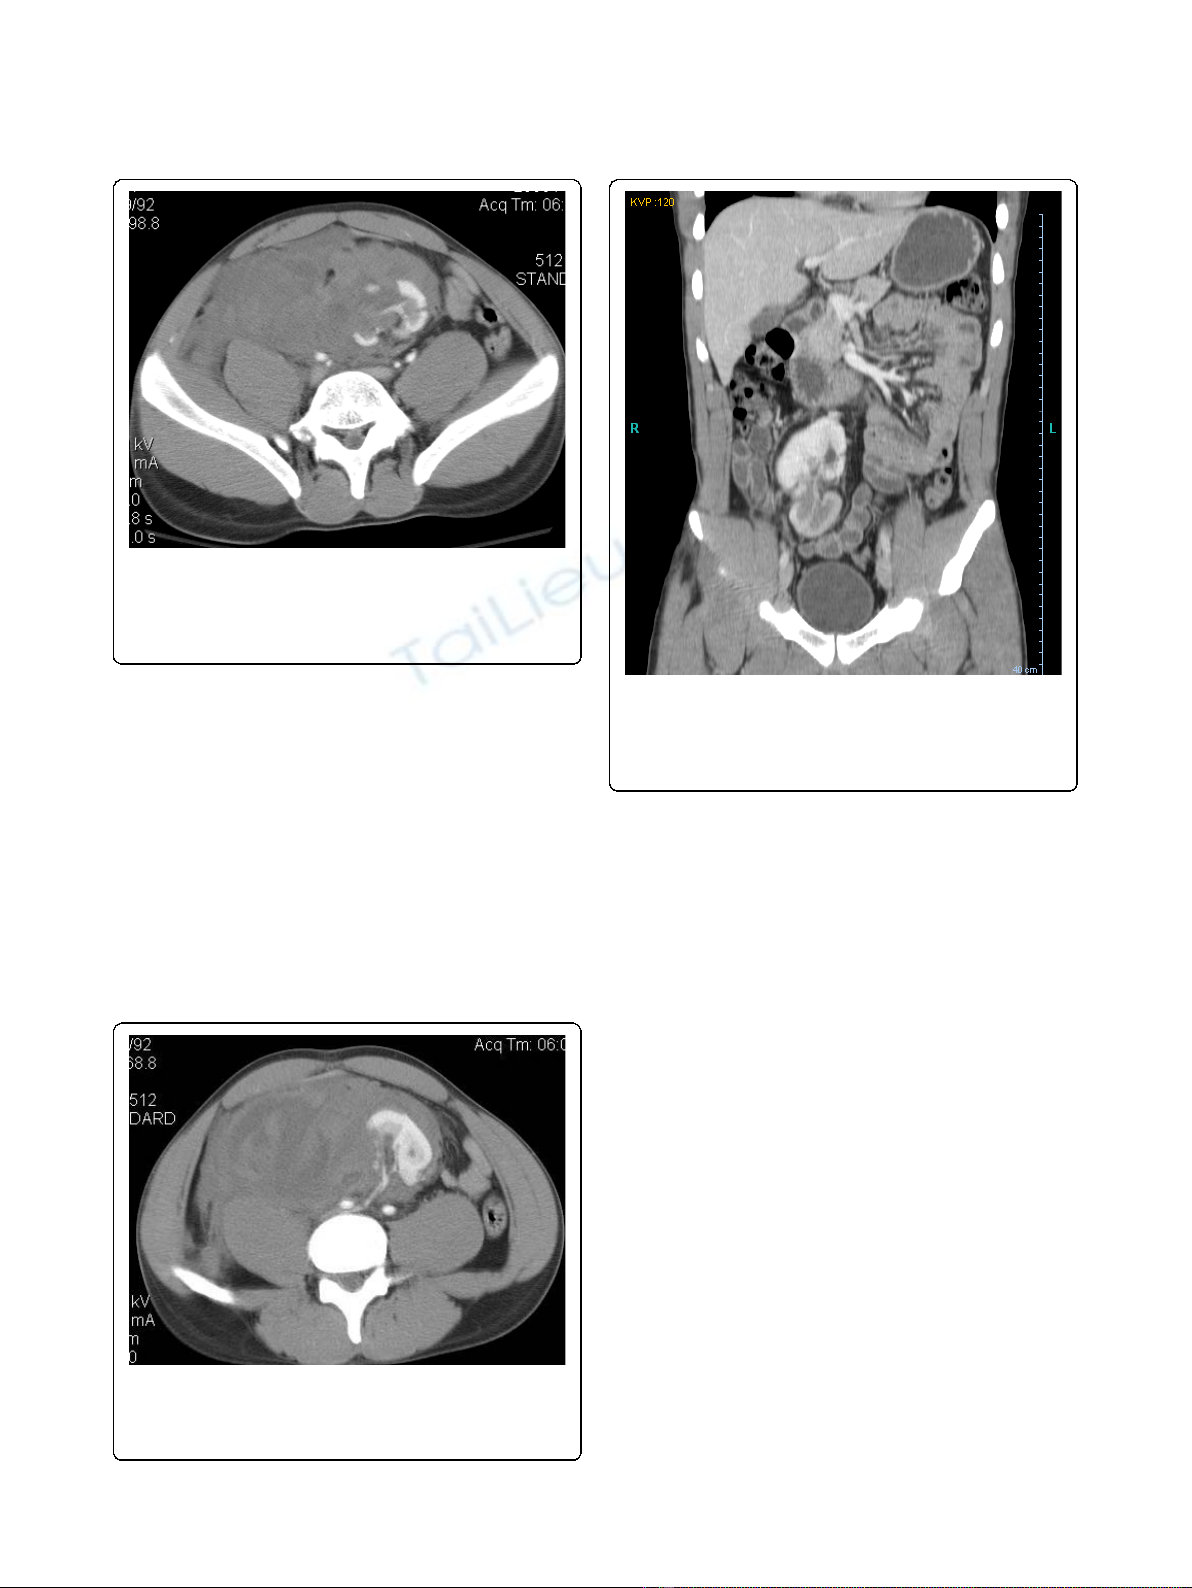

Laboratory examination revealed a hemoglobin of 12 g/

dL as well as a serum creatinine of 1.4 mg/dL. Computer-

ized tomography (CT) of the abdomen and pelvis with

intravenous contrast demonstrated a normally positioned

left kidney, multiple deep lacerations to an ectopic pelvic

kidney suggestive of a grade V injury, and a large retro-

peritoneal hematoma (Figure 1). Both kidneys appeared

equal in size, measuring approximately 11 cm in length

and 5 cm in width. The main arterial supply to the ecto-

pic kidney appeared intact, with a right renal artery origi-

nating from the right common iliac artery (Figure 2).

Figure 1 Computerized tomography of the abdomen and

pelvis with intravenous contrast demonstrating an ectopic

pelvic kidney with multiple deep lacerations (indicated by

arrows), and a large retroperitoneal hematoma displacing the

kidney to the left lower abdomen.

Figure 2 Computerized tomography of the abdomen and

pelvis with intravenous contrast showing an intact right renal

artery originating from the right common iliac artery

(indicated by an arrow).

Figure 3 Computerized tomography of the abdomen and

pelvis with intravenous contrast demonstrating resolution of

the retroperitoneal hematoma, return of the pelvic kidney to

its anatomical position in the right pelvis, as well as persistent

perfusion defects in the lower pole (indicated by an arrow).